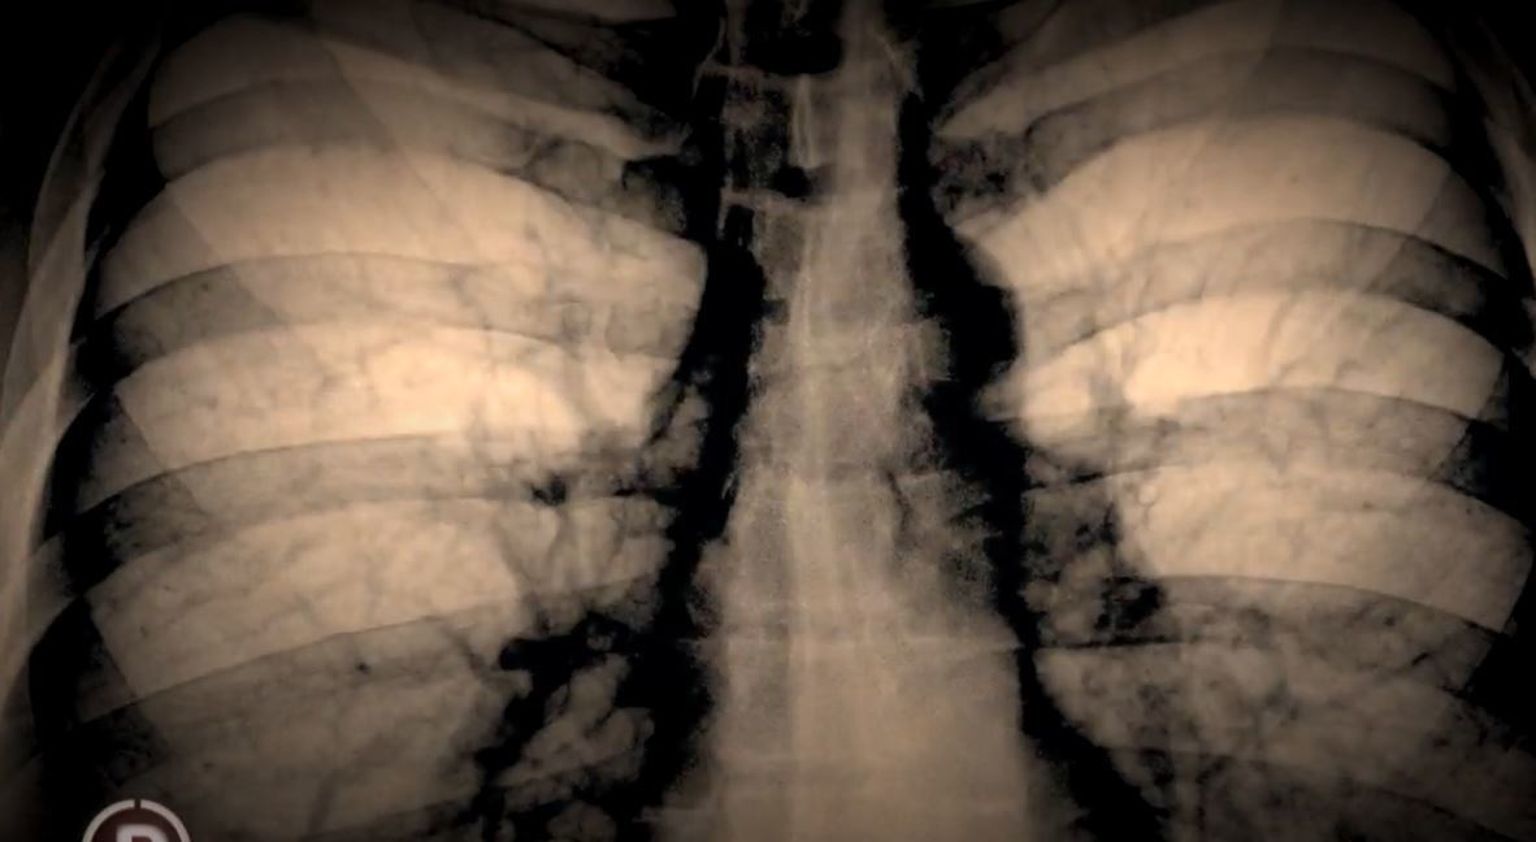

• Malena Melani živi sa cističnom fibrozom - 1 Foto: Provjereno

• Malena Melani živi sa cističnom fibrozom - 2 Foto: Provjereno

• Malena Melani živi sa cističnom fibrozom - 3 Foto: Provjereno

• Malena Melani živi sa cističnom fibrozom - 4 Foto: Provjereno

• Malena Melani živi sa cističnom fibrozom - 5 Foto: Provjereno

• Malena Melani živi sa cističnom fibrozom - 6 Foto: Provjereno

• Malena Melani živi sa cističnom fibrozom - 7 Foto: Provjereno

• Malena Melani živi sa cističnom fibrozom - 8 Foto: Provjereno

• Malena Melani živi sa cističnom fibrozom - 9 Foto: Provjereno

• Malena Melani živi sa cističnom fibrozom - 10 Foto: Provjereno

• Malena Melani živi sa cističnom fibrozom - 11 Foto: Provjereno

• Malena Melani živi sa cističnom fibrozom - 12 Foto: Provjereno